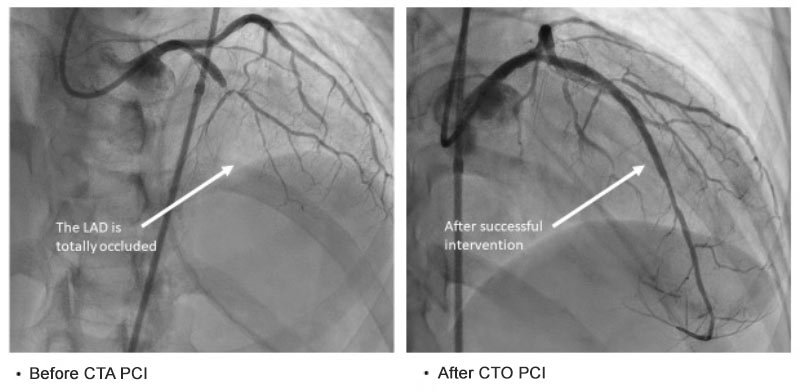

A 55-year-old female initially presented to an outside hospital with new onset heart failure, causing fluid to accumulate in her lungs. Diagnostic workup revealed a total occlusion of the left anterior descending (LAD) artery, which supplies a substantial portion of her heart.

The outside hospital team determined that Percutaneous Coronary Intervention (PCI) to revascularize the occluded LAD was not feasible, deeming it high-risk and unlikely to succeed. Consequently, the patient was discharged with guideline-directed medical therapy (GDMT) for heart failure management.

Seeking a second opinion, the patient presented to Emory University Hospital, where she was evaluated by our interventional cardiology team. After a thorough assessment, it was concluded that PCI was indeed a viable option. Emory's team is equipped with specialized expertise in managing complex coronary interventions, including Chronic Total Occlusions (CTOs).